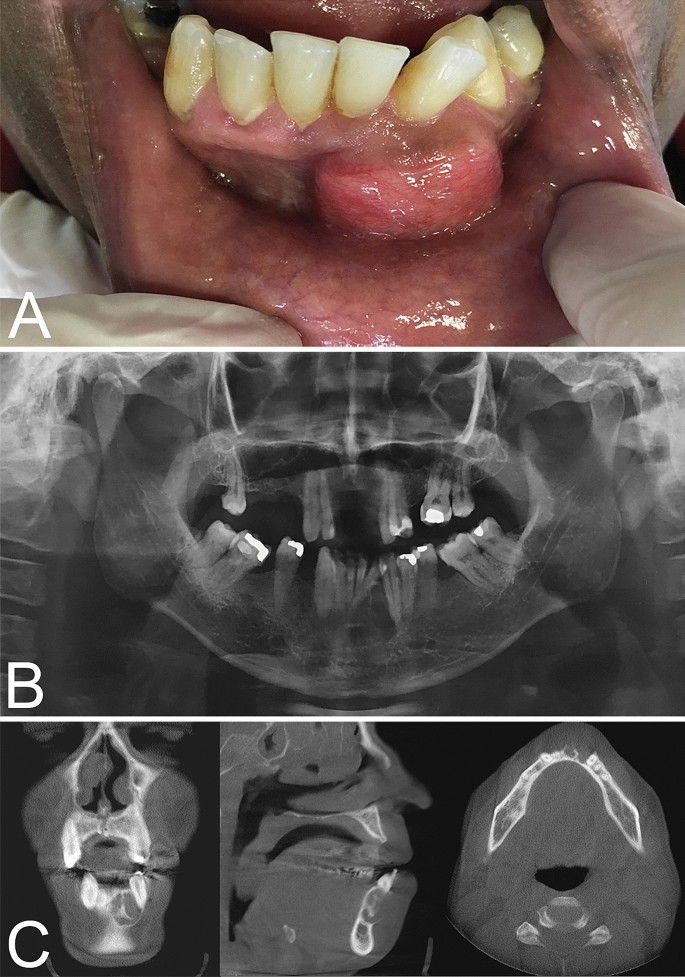

Central Odontogenic Fibroma Histology Collection 2022 Central Odontogenic Fibroma Histology Collection 2022

Central Odontogenic Fibroma Histology